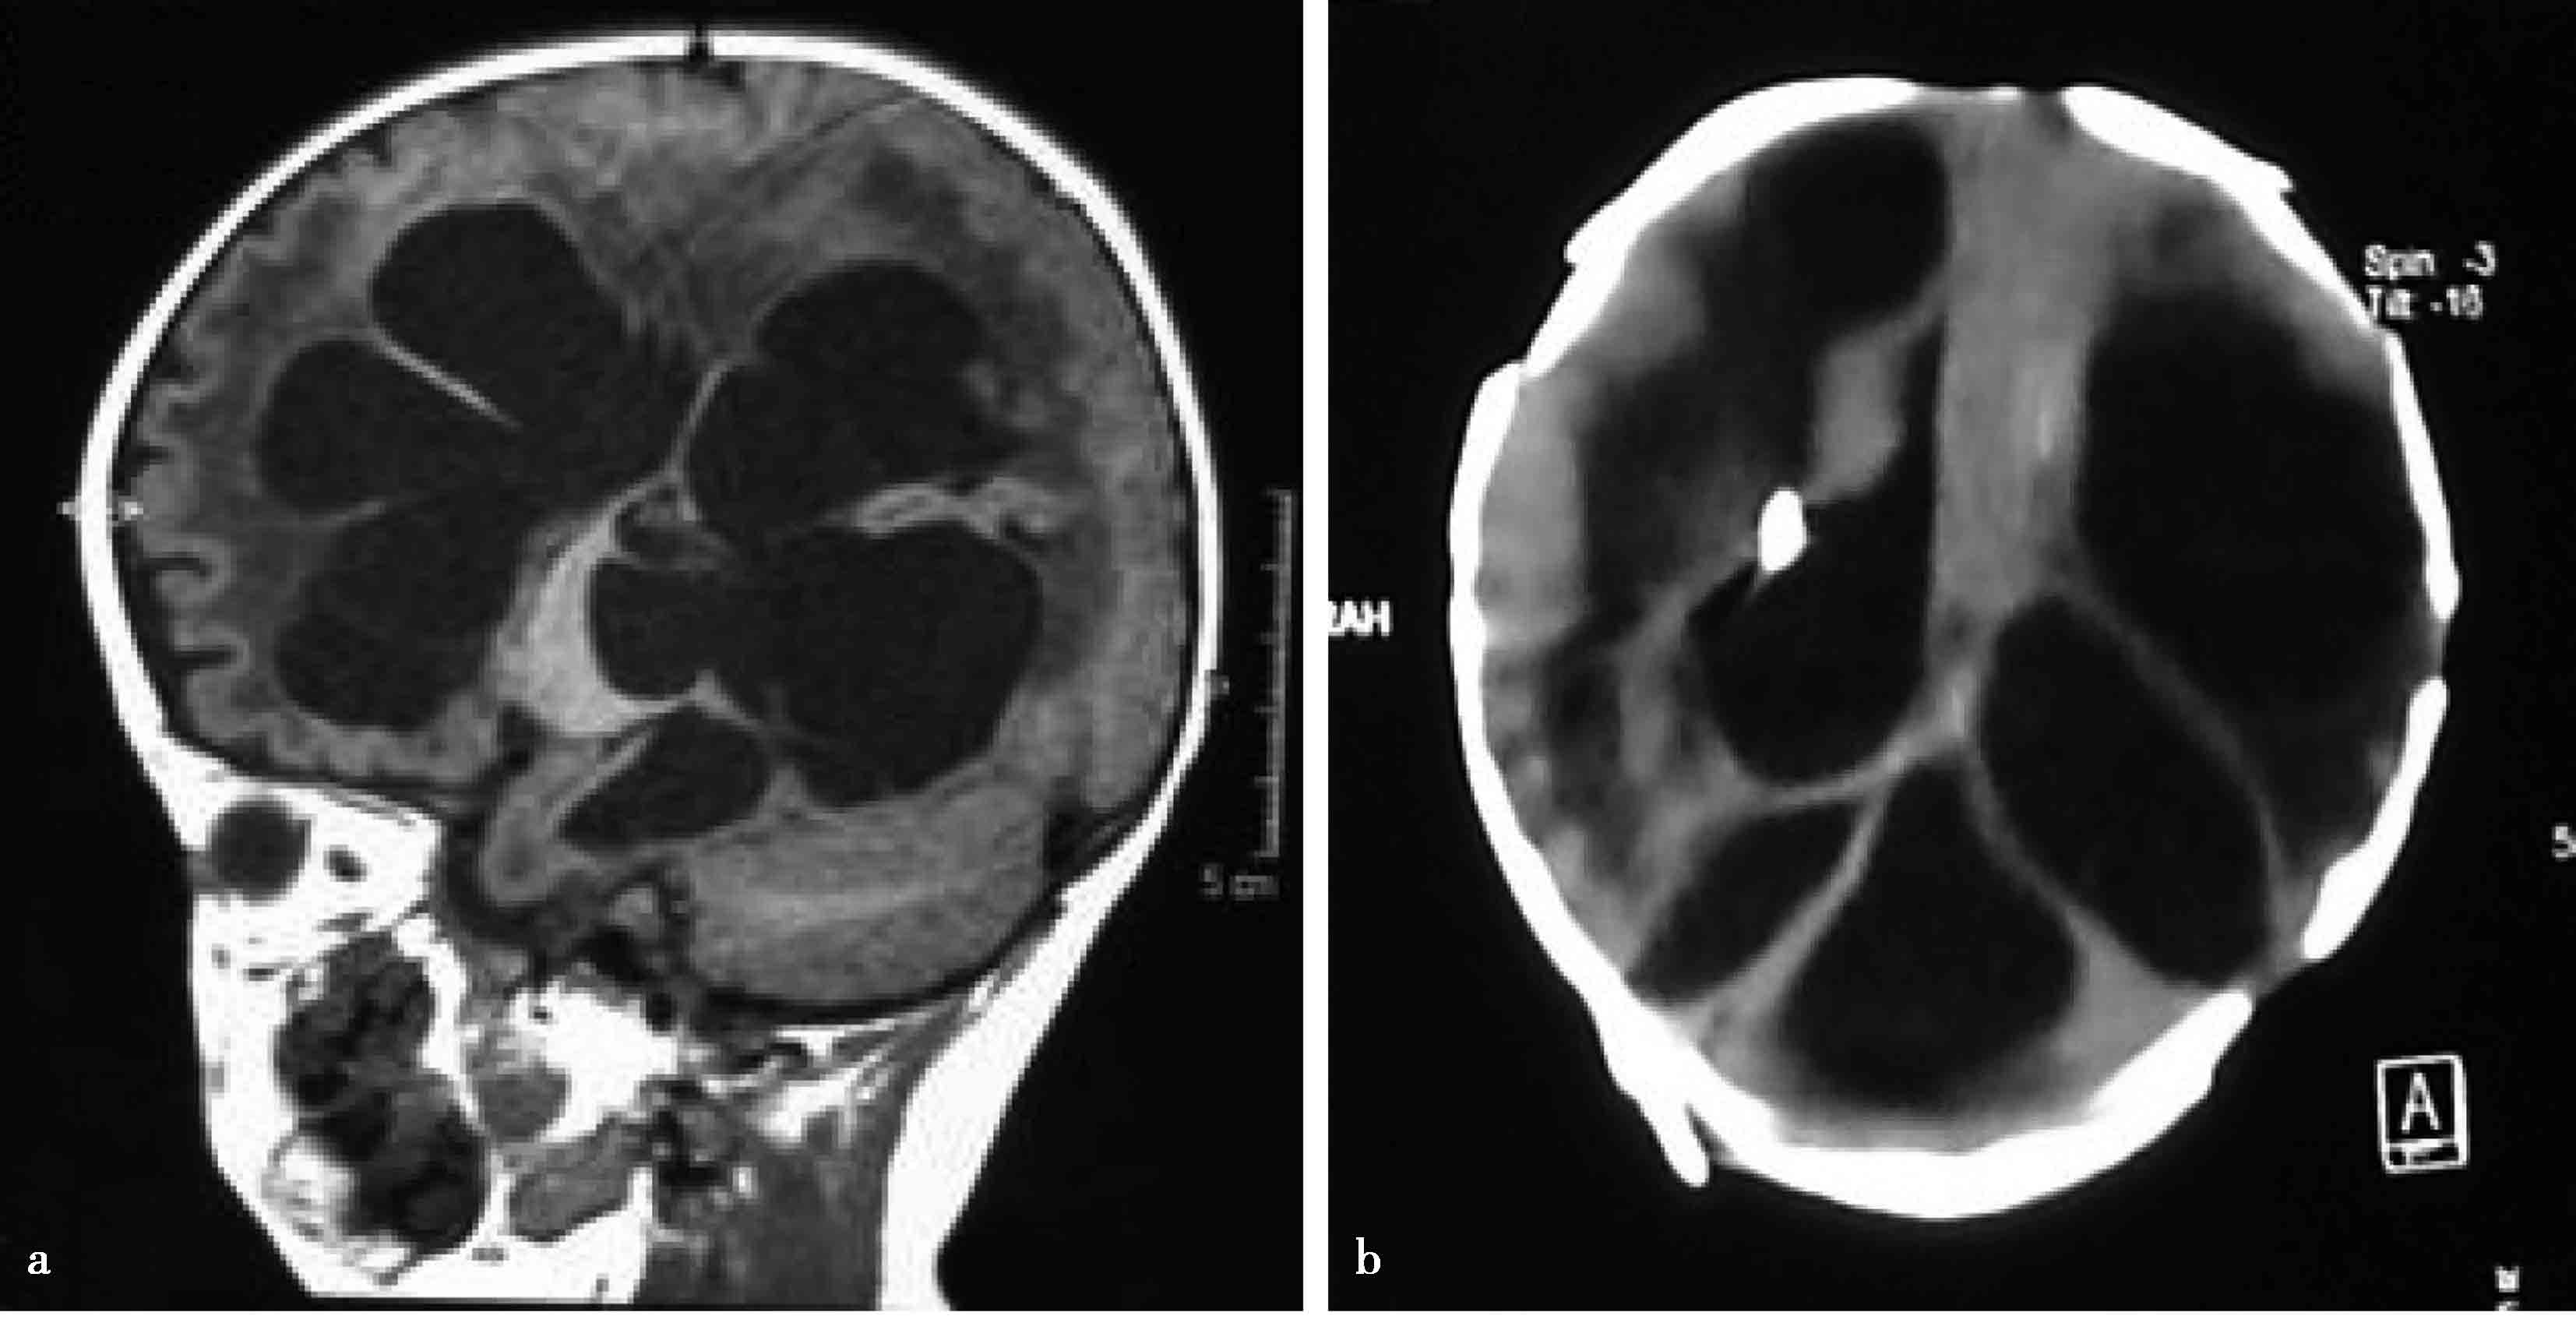

图3-1-2-10 脑室内多发分隔型复杂脑积水

a.MRI矢状位片示脑室内多发分隔;b.分流术后,CT显示脑室内多发分隔;c.脑室出血继发感染后,MRI显示脑室内多发分隔